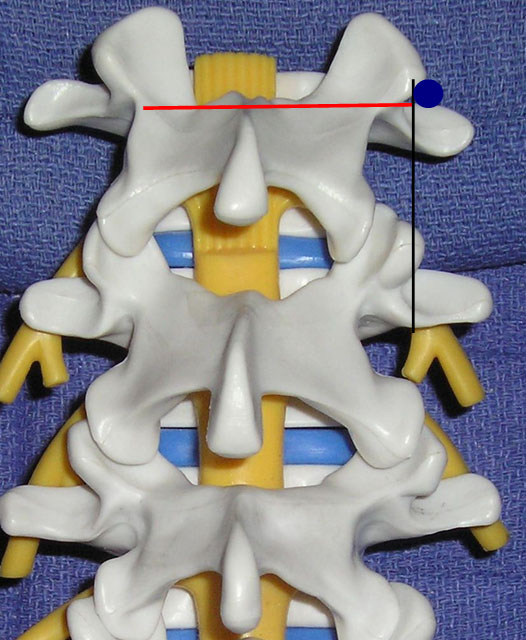

Sonoanatomy

In order to visualize the appropriate structures for lumbar medial branch blocks, a low frequency curved array transducer (2-6 MHZ) is needed.[34] The views utilized to define the sonoanatomy are the cross axis and the long axis views (Figure 11). In the long axis view, the appropriate level of the spine can be identified (Figure 12). The cross axis view demonstrates the step-off deformities between the spinous, superior articular, and transverse processes (Figure 13). In some cases the facet joint between the superior and inferior articular processes can be visualized in the cross axis view. The anatomical landmarks for the L5 dorsal ramus can be difficult to visualize with ultrasound secondary to bony artifact from the iliac crest.

Figure 11. The transducer views utilized for lumbar medial branch blocks: cross axis (red line) and long axis (black line) views. The blue circle indicates the target point.

Ultrasound Technique for Lumbar Medial Branch Blocks

Greher et al.[34] developed an ultrasound methodology for the lumbar medial branch block. First, the patient is placed in the prone position with a pillow under their abdomen to reduce the lumbar lordosis. The appropriate level of the lumbar spine is identified under the long axis view, and the level to be anesthetized is centered. The transducer is then rotated 90° to the cross axis view. The step-off deformity is seen between the superior articular process and the transverse process. Under real-time ultrasound guidance with an in plane technique, a 22-gauge spinal needle is inserted from lateral to medial (Figure 13). The insertion angle is approximately 45° to 60° to the skin. The needle is directed down to the junction between the superior articular process and the superior border of the transverse process. Once bony contact is reached the transducer is rotated back to the long axis view to confirm that the needle tip is at the cranial edge of the transverse process. Local anesthetic is then injected to anesthetize the targeted medial branch.